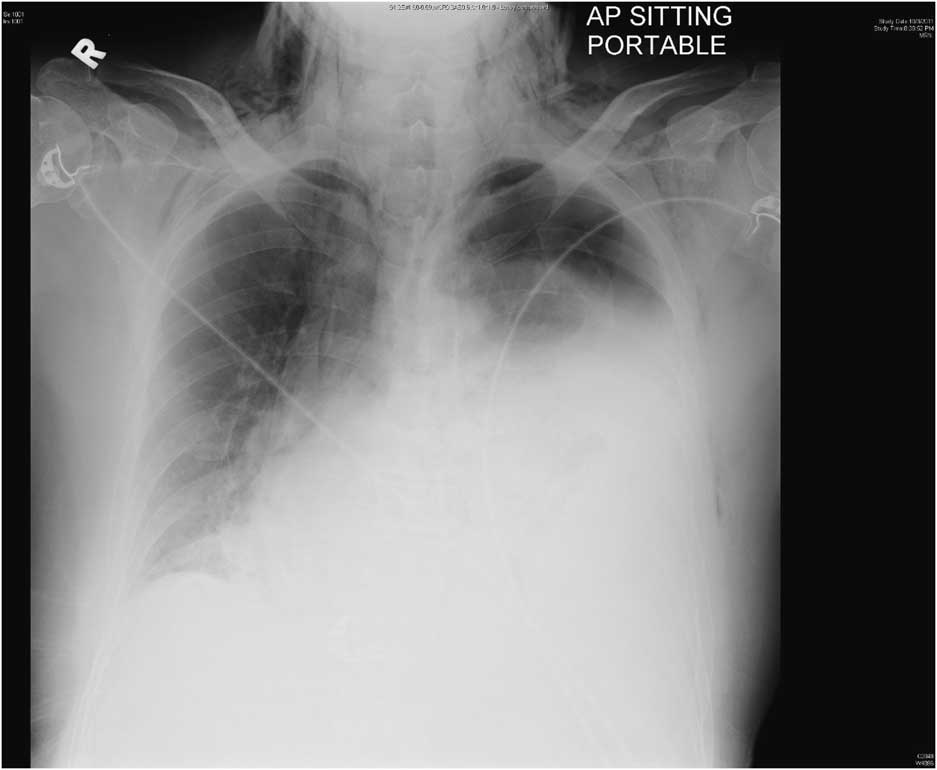

A 59-year-old shipyard worker presented to the emergency department (ED) with the complaints of mid-thoracic back pain and fever, both of 1-day duration. He was seen by a general practitioner 3 days prior for epigastric pain (now resolved) and vomiting. In the ED, he was found to be tachycardic at 104 beats per minute and normotensive. Examination found only tenderness in the left iliac fossa and decreased left-sided breath sounds. He had a total white blood cell count of 5.32×109/L with 87% neutrophils. His procalcitonin was raised at 11.2 and lactate at 10.7. A chest radiograph was obtained (Figure 1).

Figure 1 Chest radiograph showing left pleural effusion, left pneumothorax and subcutaneous emphysema involving the base of the neck and chest wall bilaterally.

Effort rupture of the esophagus (Boerhaave syndrome) is spontaneous perforation resulting from sudden increase in intraesophageal pressure such as from retching. It is rarely encountered in the ED, yet early diagnosis is crucial because survival decreases to 50% after 24 hours of delay in treatment and 10% after 48 hours.Reference Brinster, Singhal and Lee 1 Clinical presentation can be nonspecific with 50% present atypically. Retrosternal chest pain is the commonest symptom (85%);Reference Pate, Walker and Cole 2 25% to 45% may have no history of vomiting.Reference Brinster, Singhal and Lee 1 The diagnosis is suggested by chest radiograph and confirmed by computed tomogram.Reference de Lutio di Castelguidone, Merola and Pinto 3

This patient underwent a contrast-enhanced computed tomogram of the thorax and abdomen, which showed evidence of extensive subcutaneous emphysema and pneumomediastinum, a large left hydropneumothorax with passive collapse of the left lung, a mild right pleural effusion, intact tracheal walls, and a sliding hiatal hernia. He was brought to the operating room for emergency thoracotomy. Operative findings were of a perforation in the lower third of the esophagus marked by extensive necrosis along with the nearby pleura and pericardium. He underwent debridement and insertion of chest drains, an open gastrostomy, and a feeding jejunostomy. He was transferred out of the intensive care unit on Day 8.